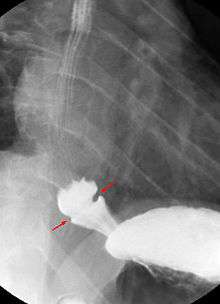

| Endoscopic image of Schatzki ring, seen in the esophagus with the gastro-esophageal junction in the background. | |

A Schatzki ring is usually diagnosed by esophagogastroduodenoscopy or barium swallow. Endoscopy usually shows a ring within the lumen of the esophagus which can be of variable size (see picture). The ring is usually located a few centimetres above the gastro-esophageal junction, where the esophagus joins the stomach. Schatzki rings can often resemble a related entity called an esophageal web. Esophageal webs also contain extra mucosal tissue, but do not completely encircle the esophagus.